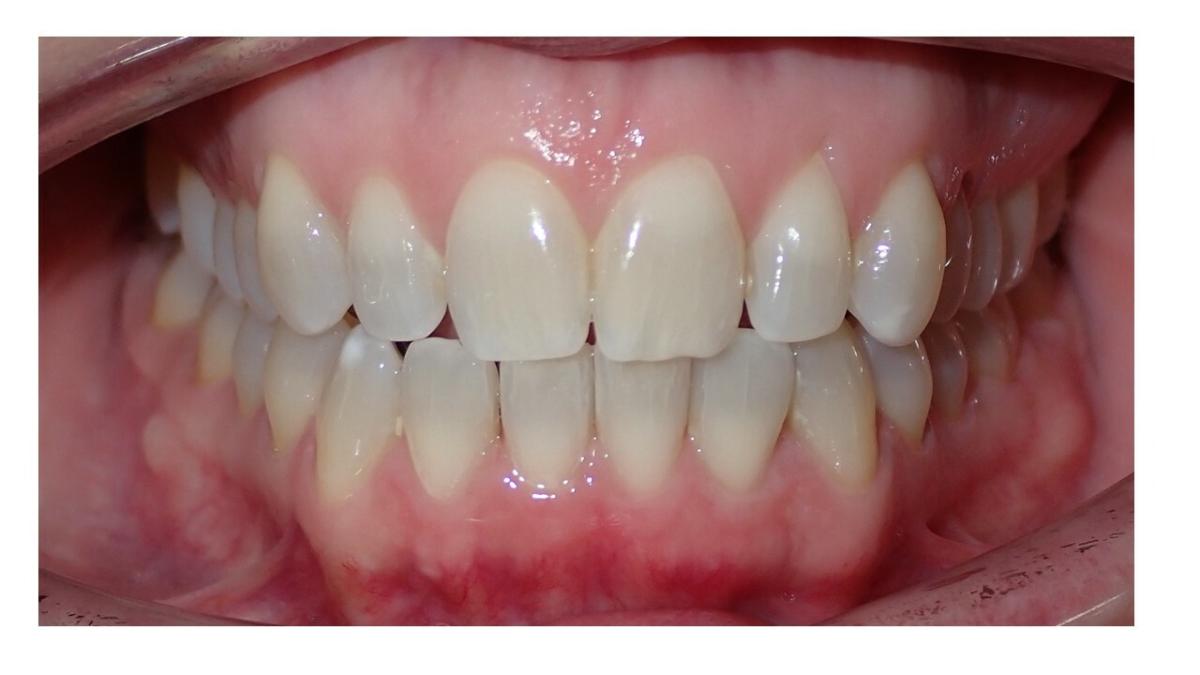

Galería de Sonrisas

large-Resultados sin que se note ortodoncia